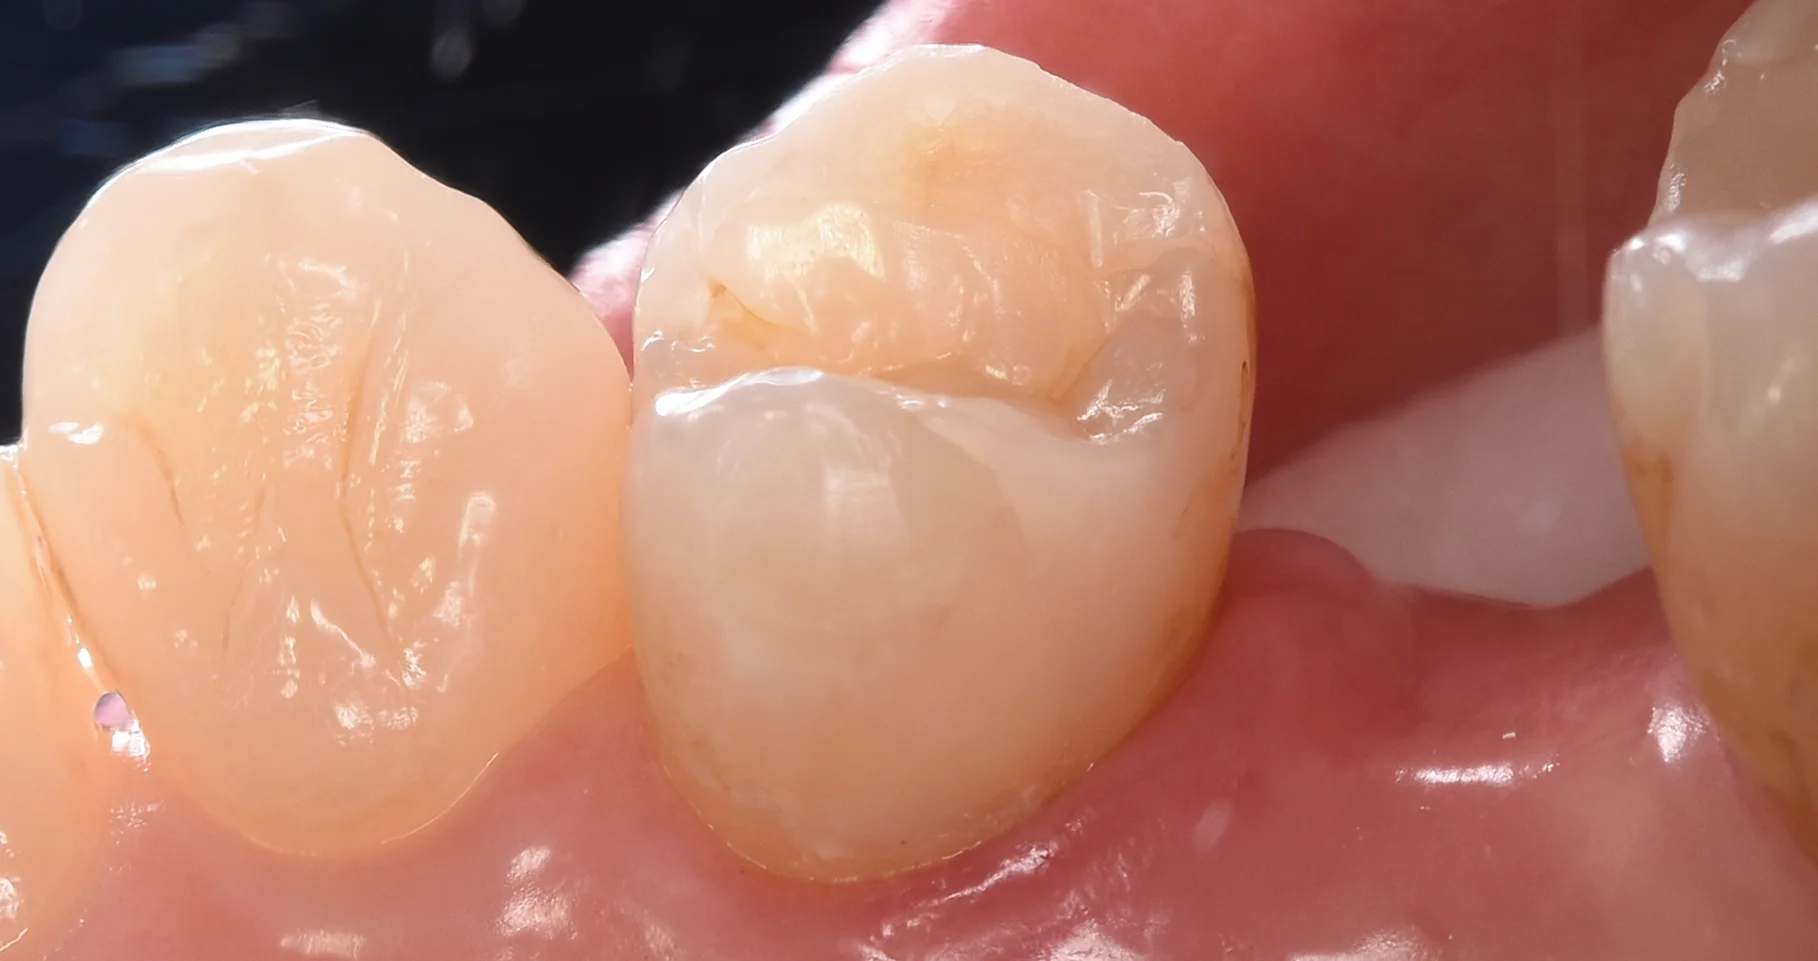

そして詰め終わったのがこちらです。

段差もなく綺麗に詰め終わることができましたヽ(゚∀゚)ノ パッ☆

4年越しの治療になりましたが、前の治療も状態としては良好ですので、今後も長く使っていけると思います!

4年前との比較がこちらです。

カメラが変わっているので全く色合いが違っていますが、ほぼほぼ良好な変化を辿っていると思います。